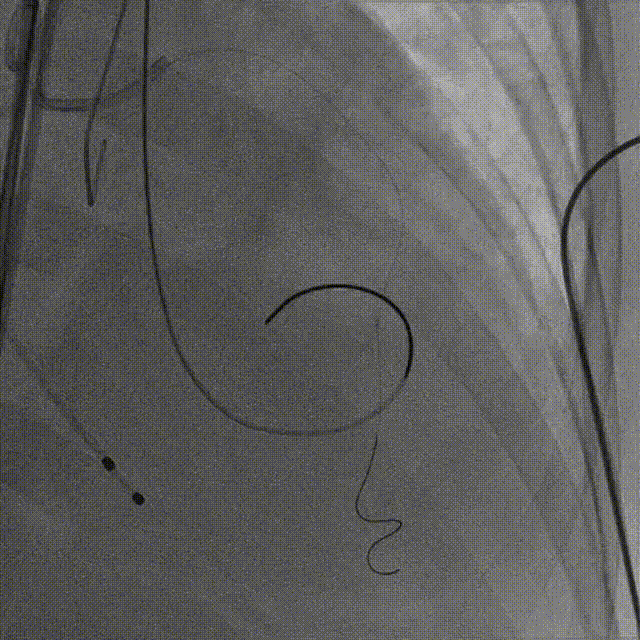

手术过程概览

7.输送器过弓

8.瓣膜定位

9. 工作位评估冠脉

10.右冠行烟囱支架技术